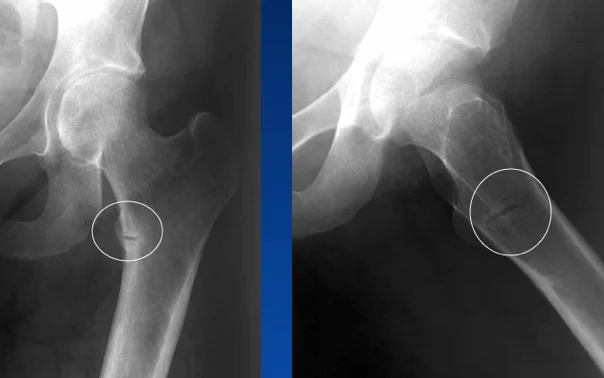

Stress Fractures

- Bone reacts to repeated loading, may become fatigued & a crack develops

- Fatigue fractures

- Abnormal stress or torque on a bone that has normal elastic resistance

- Examples:

- military recruits, athletes, ballet dancers

- Insufficiency fractures

- Normal muscular activity stresses a bone that is deficient in mineral or elastic resistance

Stress Fracture Details

- Usually Transvers

- 2nd metatarsal

- Tibia

- Fibula

- In osteopenia, osteomalacia

- Neck of femur

- Ribs

- Neck of humerus

- Scapula